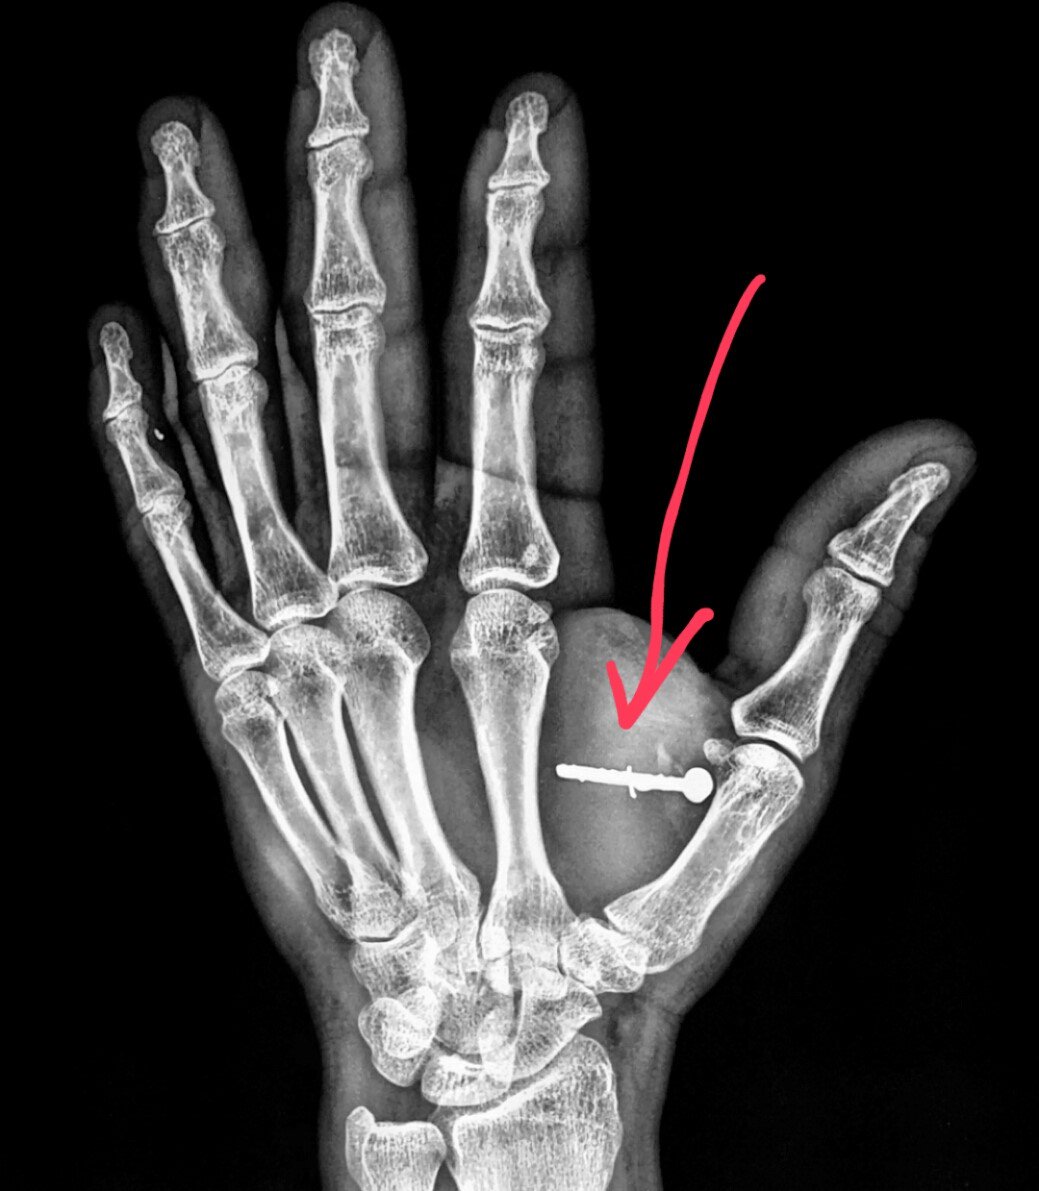

From www.researchgate.net

Radiologic appearance of staplegun injury. Download Scientific Diagram Staple Gun Injury The answer is not a simple yes or no. While it is unlikely for a staple gun to cause fatal harm, it is still a dangerous tool that can cause serious injuries if not used properly. Wood, plastic, or metal shards. Nail guns were introduced in both industry and the general public back in 1959. Carpenters, roofers, and manufacturing jobs. Staple Gun Injury.